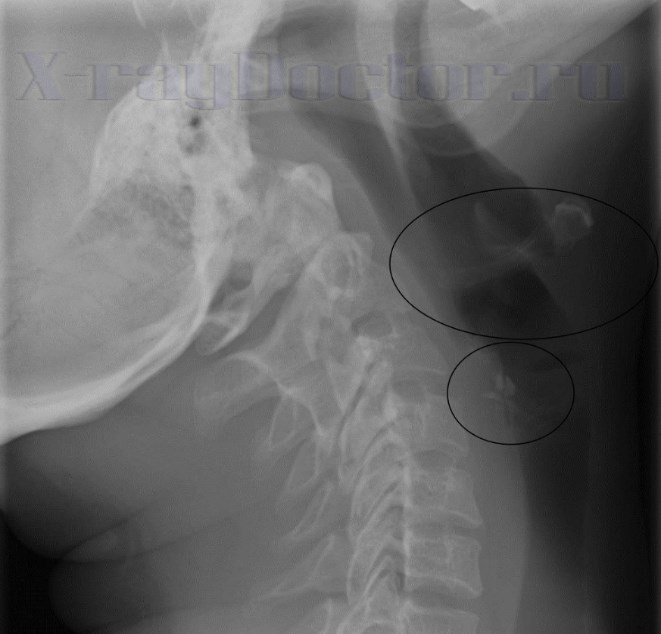

Аденоиды на снимке в боковой проекции прослеживаются нечетко. При выполнении дополнительного исследования (томографии) можно четко проследить увеличение глоточных миндалин. С помощью томографических срезов прослеживается структура органов на разных уровнях.

Для четкой визуализации структур следует выполнять функциональное обследование – на вдохе и выдохе. Если делать снимок при вдохе и произношении звуков «у» или «и», можно увидеть голосовые связки. Их неравномерность и увеличение подвижности свидетельствует о патологических изменениях (ларингит, рак, инородное тело).

Томограмма на глубине 10 мм позволяет четко проследить структуру тела подъязычной кости, переднего отдела голосовых связок и основания надгортанника. Воздушный столб гортани и грушевидные синусы четко видны на снимке в боковой проекции.